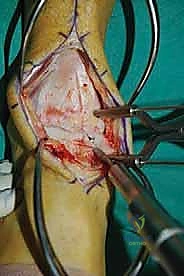

الغوص العميق في جراحة الطعم الخيفي الهيكلي (Structural Allograft Reconstruction)

يهدف هذا الإجراء العبقري إلى استبدال الغضروف والعظم التالفين والميتين بنسيج سليم تماماً مأخوذ من متبرع متوفى (طعم خيفي - Allograft). هذا الطعم يتم تعقيمه وحفظه في بنوك الأنسجة العالمية وفقاً لأعلى المعايير الطبية الصارمة لضمان خلوه من أي أمراض معدية والحفاظ على حيوية الخلايا الغضروفية.

- الترميم التشريحي الحقيقي: يسمح باستعادة الشكل الهندسي الدقيق لعظم الكاحل، بما في ذلك المنحنيات المعقدة لكتف التالوس.

- توفير غضروف طبيعي (Hyaline Cartilage): الغضروف المزروع هو غضروف زجاجي طبيعي،